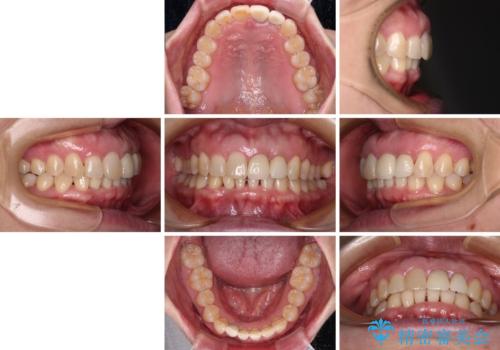

- 下顎前歯が抜けそうとのことで来院された患者様です。

初診の状態ではすぐにでも抜けそうな状態で、インプラントによる補綴治療を行うこととしました。

インプラント治療に際し、前歯の叢生に対する矯正治療を提案したところ、興味を持たれたので、インビザライン・ライトによる矯正治療を行うこととしました。

抜歯後にスペースができると恥ずかしいため、抜歯した歯を接着剤で固定した上で矯正治療を行い、その後インプラントやオールセラミッククラウンの装着を行うこととしました。